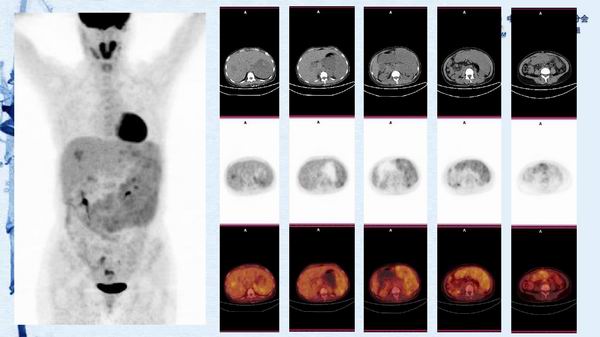

病例81:原发性脾血管肉瘤伴肝血管瘤一例-【CSNM继教学组】郑堃 北京协和医院